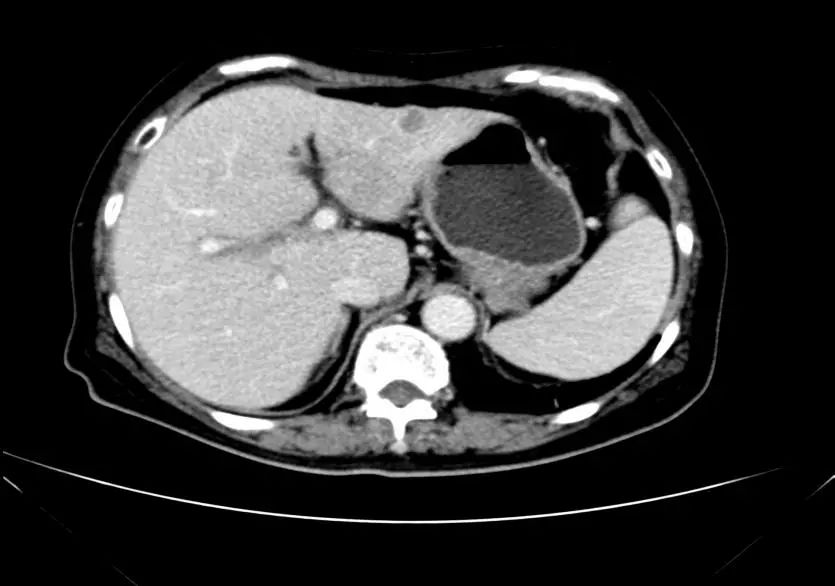

• CT示:肝转移

• MR示:

临床分期:cT4bN1M1,cStageⅣ